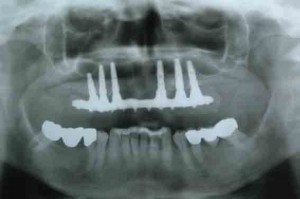

Gli impianti dentali rappresentano la prima scelta nel ripristino funzionale delle zone edentule, siano esse singole o multiple; il successo implantare può raggiungere il 98% dei casi. Tale...

Le procedure di progettazione virtuale degli impianti e di chirurgia guidata stanno diventando molto popolari nella pratica clinica quotidiana. L'utilizzo della tecnologia CBCT permette una diagnosi...

Scarsa qualità di osso, quale impianto e quale strategie adottare? Le risposte ai quesiti dalla letteratura Oggi gli impianti sono riconosciuti dalla comunità internazionale come un...